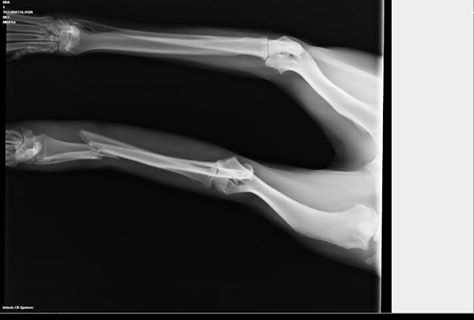

Minera se encuentra en una casa de acogida donde ha estado recuperándose de su operación de una de sus patas, pero ya no la pueden tener mas tiempo, y buscamos para ella urgente acogida o adopción o tendrá que volver al albergue.